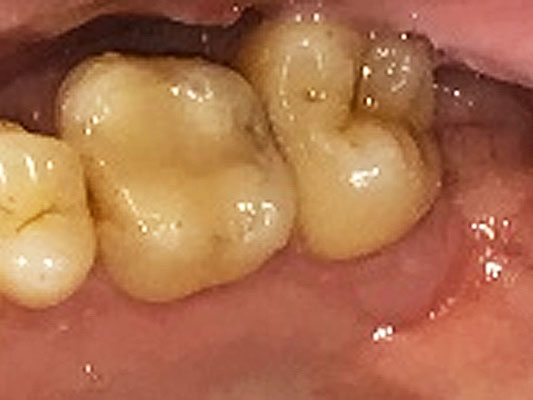

虫歯治療前

虫歯治療後

患者さんは40代の男性で、マウスピース矯正中でした。マウスピース矯正は手軽な反面、一日の指定時間(通常22時間前後)は透明なマウスピースを装着する必要があるため、マウスピース矯正中に虫歯のお悩みに直面する患者さんが多い治療です。矯正専門のクリニックでは自院で精密な虫歯治療ができない、虫歯治療をすることで歯の形が変わってしまいマウスピースの作り直しが必要になるなど、矯正中の虫歯治療が難しい場合が多くあります。

この患者さんもマウスピース矯正中に虫歯治療の必要があり、左上6番の虫歯治療することになりました。デジタルの歯科治療に豊富なノウハウを持つ恵比寿・広尾歯科はマウスピース再製作の費用や矯正期間遅延の心配することなく、矯正中も虫歯治療をおこなうことができます。